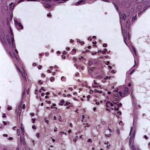

. The typical histologic features are best observed in erythematous skin adjacent to early blisters. In these zones, neutrophils accumulate at the tips of dermal papillae. With an increase in size to microabscesses, a significant admixture of eosinophils may be noted. As microabscesses form, a separation develops between the tips of the dermal papillae and the overlying epidermis; thus, the early blisters are multiloculated . The presence of fibrin in the papillae may give them a bluish appearance. Within 1 to 2 days, the rete ridges lose their attachment to the dermis, and the blisters then become unilocular  and clinically apparent. At this time, the characteristic papillary microabscesses may be observed at the blister periphery. For this reason, the inclusion of perivesicular skin in the biopsy specimen is of

utmost value. The papillary dermis beneath the papillae may have a relatively intense inflammatory infiltrate of neutrophils and some eosinophils. Many neutrophils may exhibit leukocytoclasis. Subjacent to this, a perivascular infiltrate composed of lymphocytes, neutrophils, and eosinophils may be apparent. the diagnostic finding of papillary microabscesses may not be present in all patients. Apoptotic keratinocytes may be noted above the papillary microabscesses.